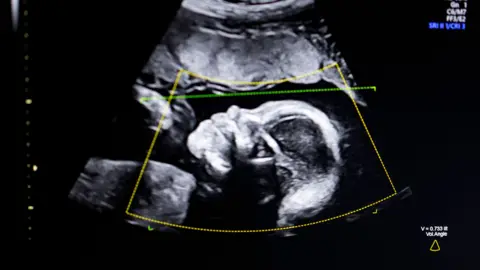

Getty ImagesSome high-street clinics are putting lives at risk by allowing unqualified non-specialists to carry out baby scans, the Society of Radiographers (SoR) has warned.

It is concerned that anyone using an ultrasound machine can call themselves a sonographer and offer the service – often sold as a reassurance, souvenir or sexing scan – ahead of the routine 20-week NHS check.

The president of the SoR, Katie Thompson, said there were some “really great” private services offering checks with properly trained staff, but she was particularly concerned about the growth of pop-up clinics in shopping centres and on high streets selling souvenir images or scans to reveal the sex of the baby.